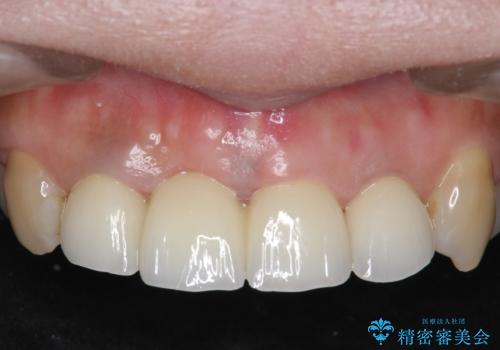

- オールセラミッククラウン(スペシャル)…¥130,000×4、仮歯…¥10,000×4、ファイバーコア…¥20,000×3、精密根管治療費別途費用は治療当時の料金となります

前歯の補綴ではオールセラミッククラウンを希望される患者様が多いですが、オールセラミッククラウンの中でも、エコノミー、スタンダード、スペシャル、エクセレントとランクがあります。

その中でも特に審美性が高いのがスペシャル、エクセレントです。スペシャル、エクセレントは口腔内写真をもとに熟練の技工士が、患者様の口腔内に合わせたオーダーメイドのクラウンを製作致します。